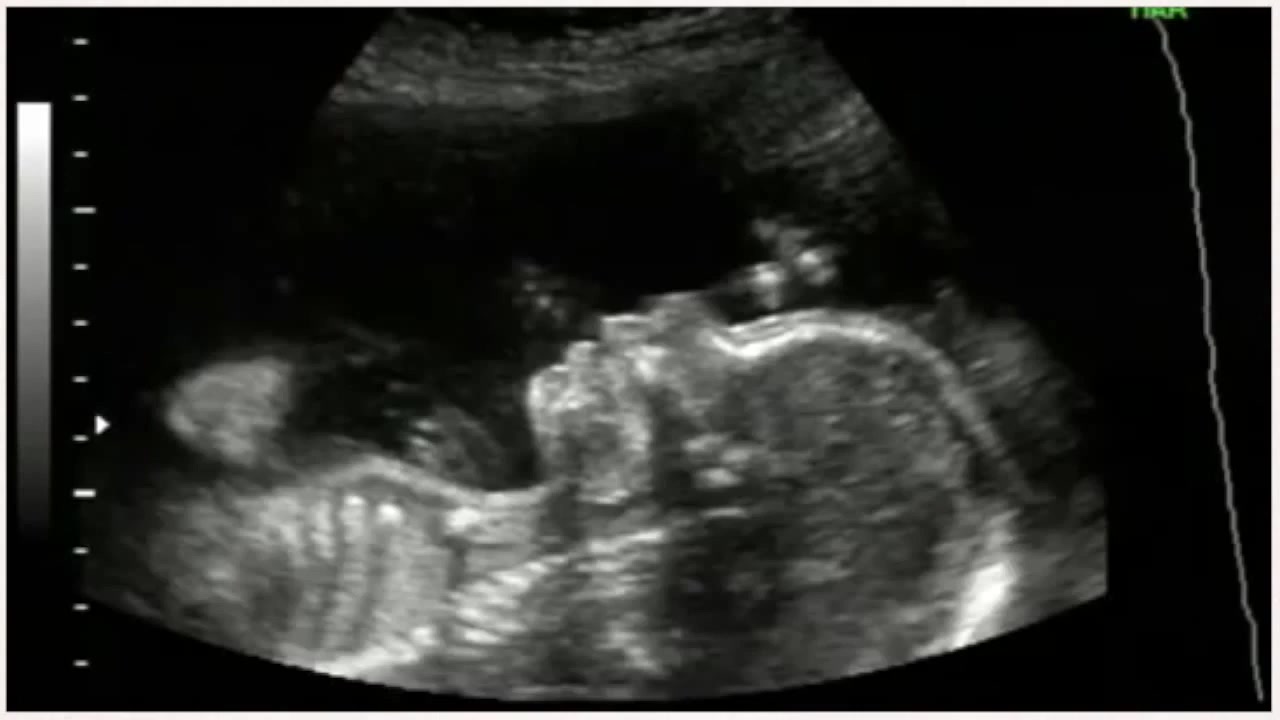

Узи 22 недели